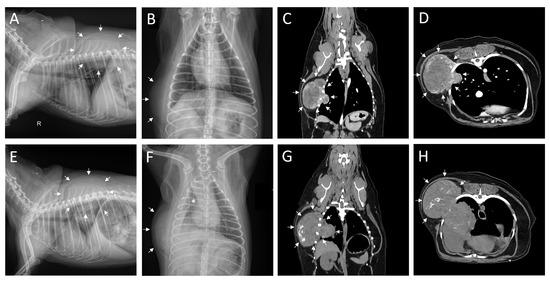

2. Case Description